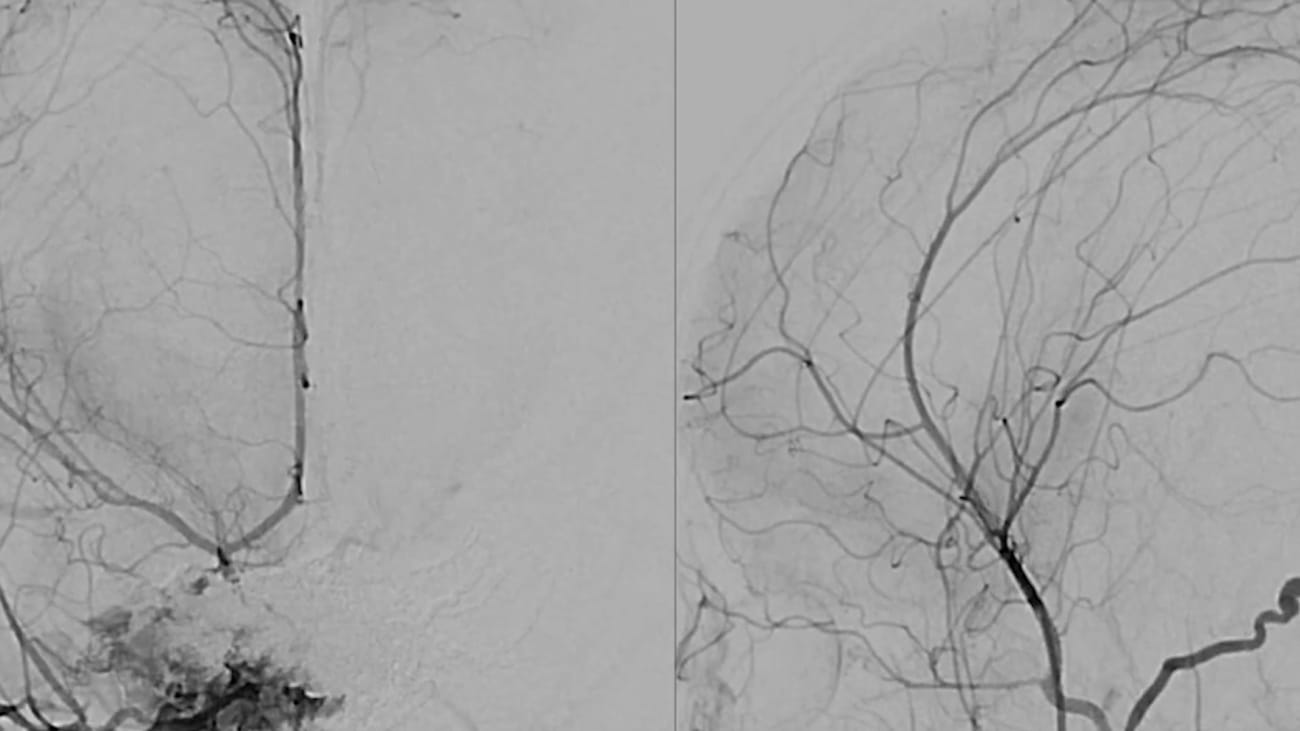

A 2-month-old female neonate presented to Mount Sinai Kravis Children’s Hospital for life-saving treatment of dural sinus malformation, hydrocephalus, and acute intracranial hemorrhage. See how a team led by Johanna T. Fifi, MD, performed a staged transarterial endovascular embolization with no subsequent neurological deficits and achieved complete obliteration of the dural sinus malformation.